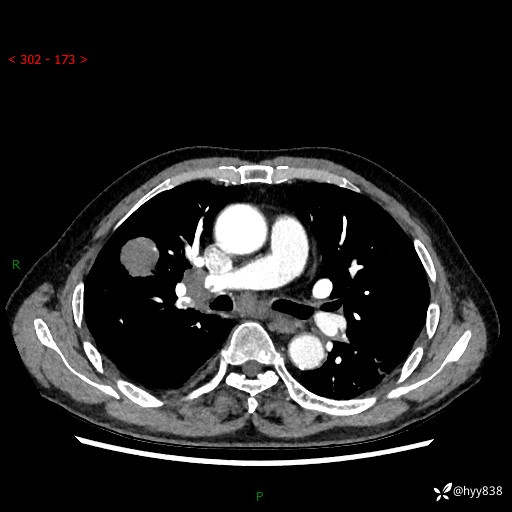

69岁/男,间断咳嗽伴气促、下肢水肿。临床拟诊肺栓,偶发肺均质强化结节--结果公布

【患者信息】:69岁/男

【主诉】:间断咳嗽伴气促、下肢水肿2周

【现病史及既往史】:患者2周来无明显诱因出现咳嗽,咳少量白痰,不易咳出,伴有气促,呈间断发作,症状与活动费力相关,以夜间为甚,不能平躺入睡,偶有憋醒,无胸闷胸痛、无发热、无头晕、头痛等不适,伴有双下肢中度水肿,就诊于当地县人民医院门诊,完善相关检查提示:左下肢深静脉血栓形成,未予以特殊处理,今患者为求进一步诊治来我院就诊,拟“心衰”收入我科。 起病以来,患者精神、饮食、睡眠可,大小便如常,体力明显下降,体重未见明显减轻。

【检查】:胸部CT增强